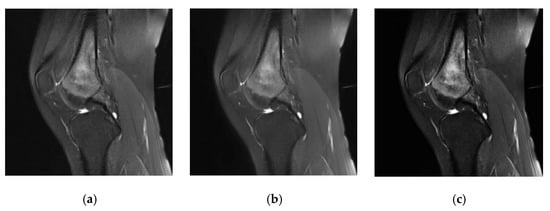

- This study proposes an auxiliary segmentation method of osteosarcoma in MRI images based on denoising and local enhancement, improving the accuracy and speed of segmentation and reducing resource consumption.

- We use the medical denoising model Eformer to remove noise and then localize and enhance the osteosarcoma region in MRI images. After preprocessing, the tumor region in the MRI image will be clearer and the boundary can be enhanced. Finally, an efficient and accurate network DFANet is used to segment osteosarcoma in MRI images.

4.5. Evaluation of Segmentation Effect